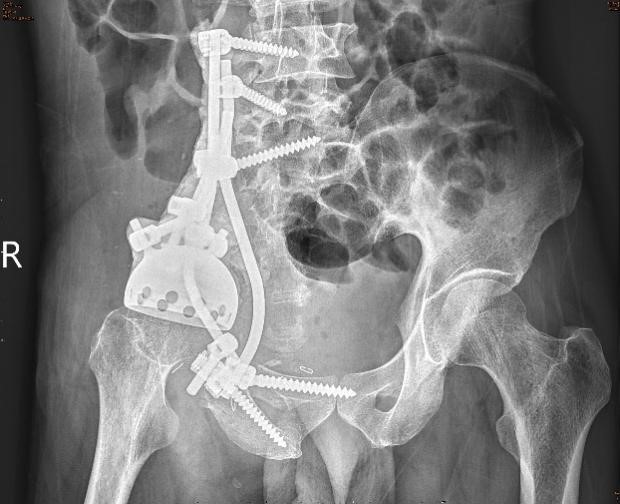

6月8日,周某被送上手术台。术中,医护团队在麻醉后先经输尿管逆行插管,进行“右半骨盆+盆腔+腹腔巨大软骨肉瘤整块切除+半骨盆假体重建术”。

多位医生接力上台,有条不紊地分离保护髂外血管,凿断耻骨、坐骨支,切开骶髂关节,使肿瘤能够移动,随后包膜外分离肿瘤周围,同时将与腹膜黏连紧密的部分肿瘤一起完整切除。

切除肿瘤后,中山一院胃肠外科吴晖副教授协助探查腹腔及修补腹膜,在多学科团队协助下,进行半骨盆假体重建,保留右侧肢体及功能。